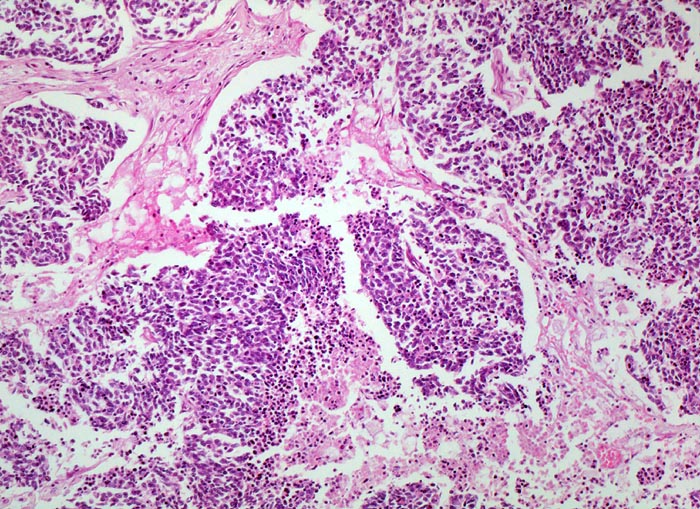

PathoPic ID 4721 - kleinzelliges Bronchuskarzinom: Tumornekrosen

kleinzelliges Bronchuskarzinom: Tumornekrosen

maligner Tumor

Lunge

Fokale

Tumornekrosen.

Inoperables metastasierendes Bronchuskarzinom. Nikotinabusus 70 Packyears.

Histologie

100